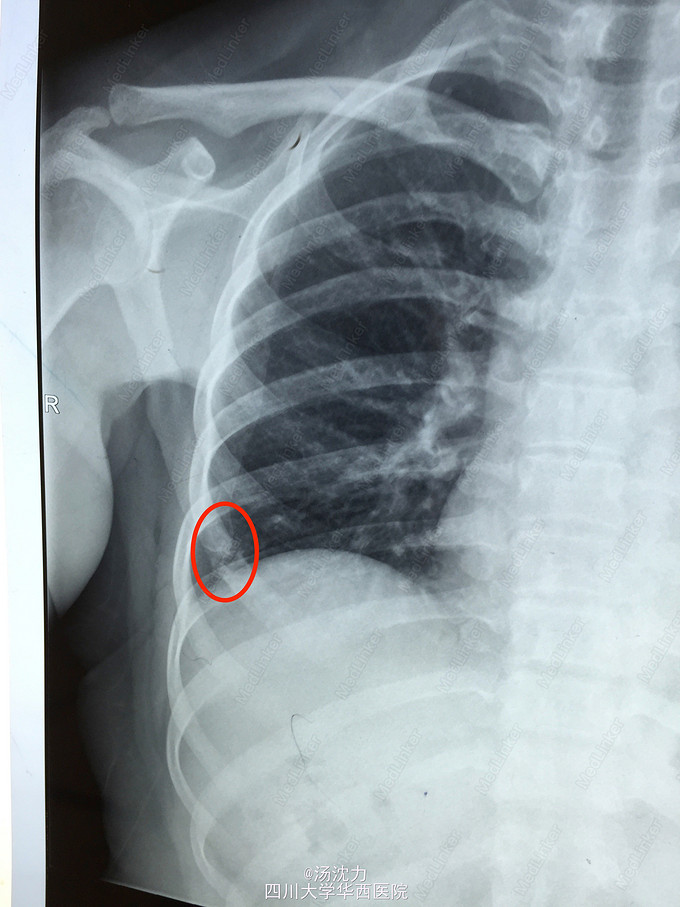

肋骨转移还是陈旧性骨折?

患者乳腺癌术后规律复查,未诉骨折病史及明显不适。最近三年胸片如图。2年前曾行骨扫描,怀疑该处为陈旧性骨折。

2年前和1年前的病变比较起来比较像骨折修复的感觉,但是今年的胸片变化看着又像是明显的溶骨改变,加上患者未诉明显的外伤史,所以更倾向于怀疑是转移瘤。